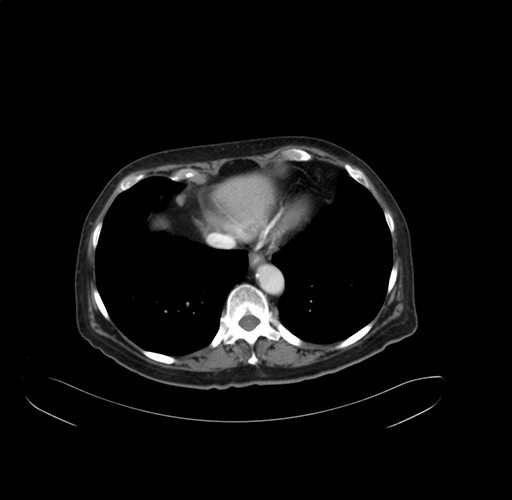

Pre-Chemo: Axial Venous

Axial Venous